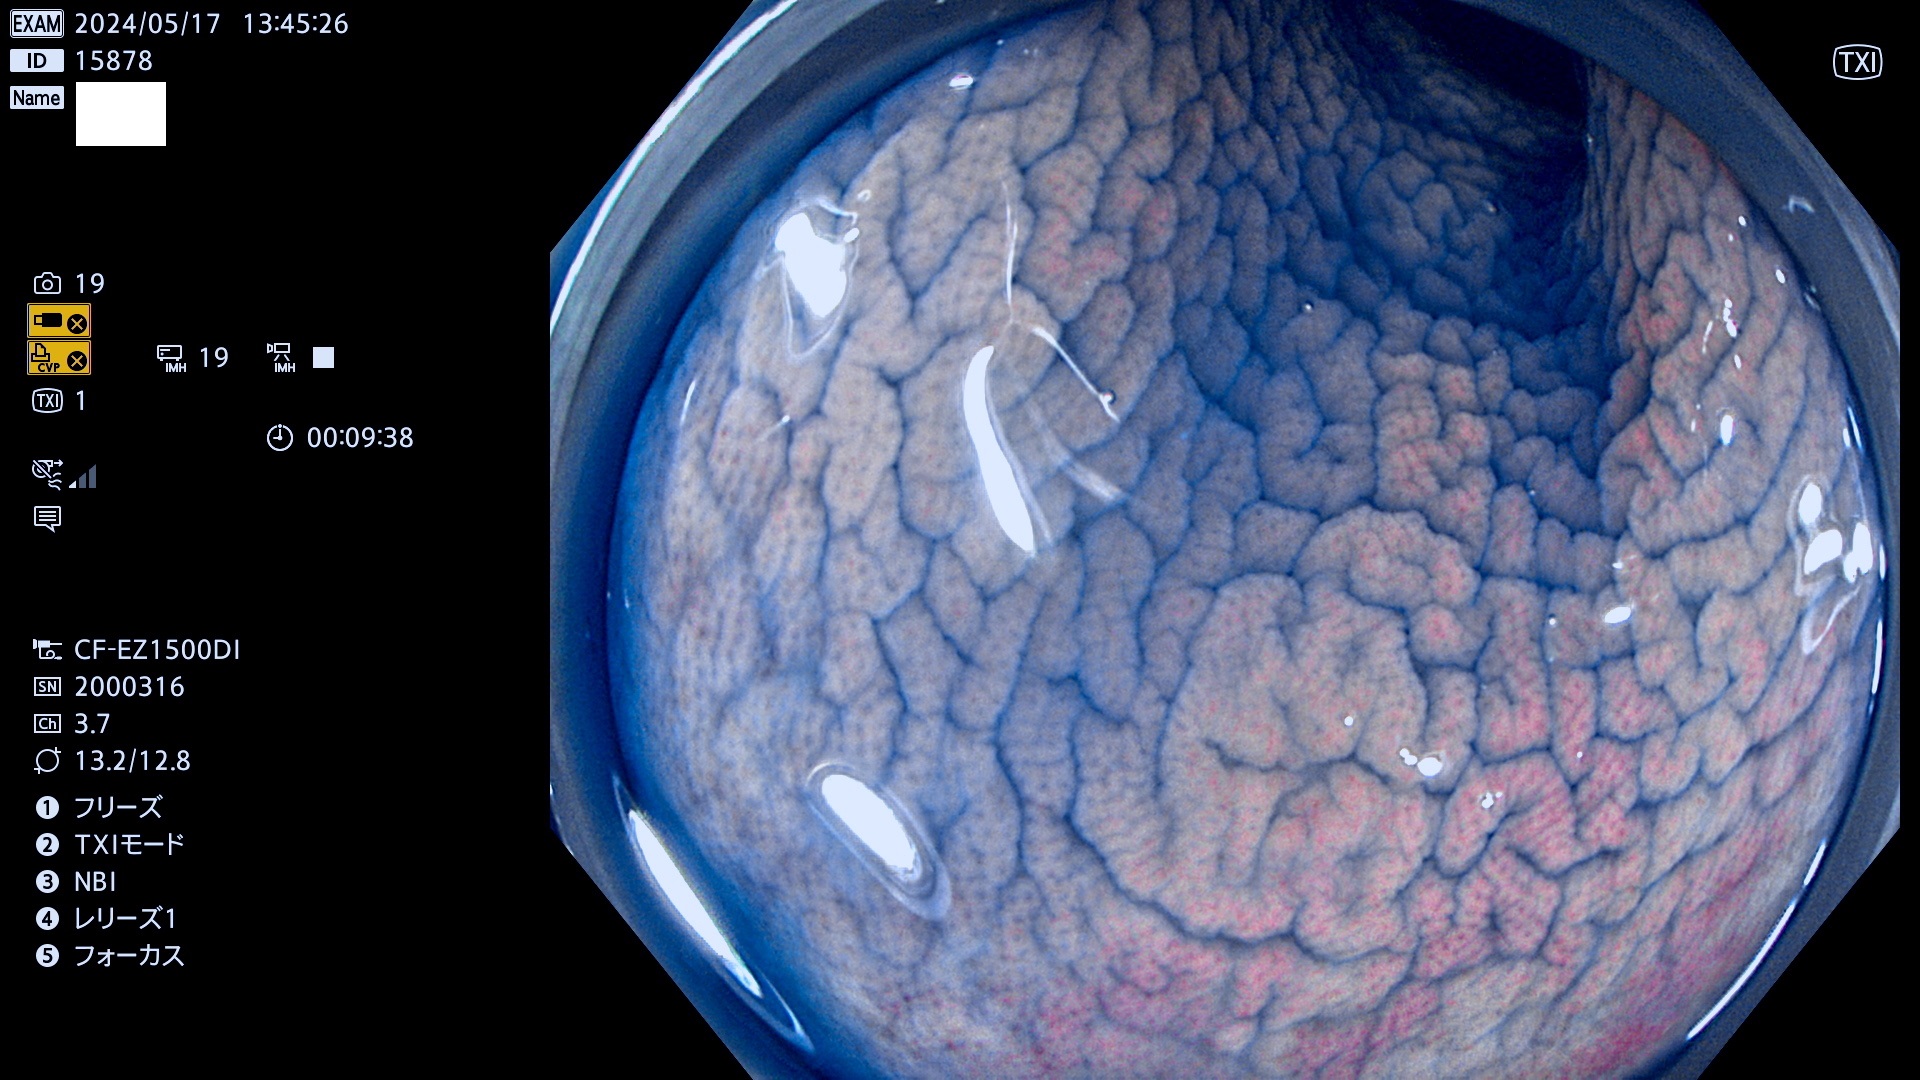

以下は当院で経験した「ビランと鑑別の難しいUc型腺腫」です(全て、病理で腺腫を確認済み)。

このような病変は表面を拡大観察しても診断は不可能であり、現在の内視鏡診断の「限界を超えた病変」と言えます。現実的な対策は「典型的なビランと異なる」と感じたら、「コールド法で積極的に切除する」ことと考えます。もちろん「結局はビランだった(不要な過剰切除だった)」ということもあります。しかしコールド法なら重篤な合併症は稀であり、医師は切除を躊躇すべきではないと考えます。